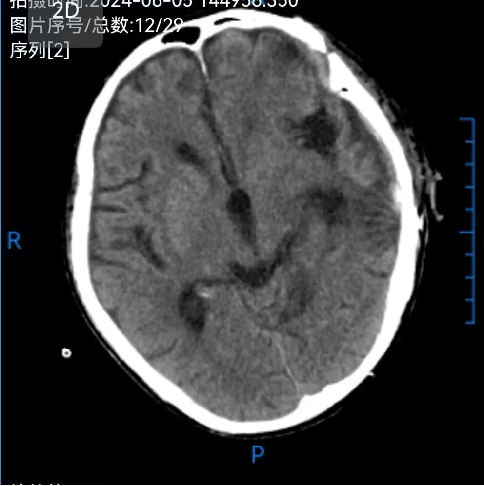

术前: